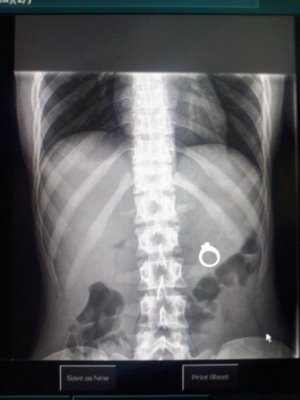

Bottoms Up, Rings Down!

Putting a ring inside your girl friend’s Wendy’s Frosty may seem romantic, but when you and your friends encourage her to chug it, you might just ruin the surprise. At least, that’s what happened to Reed Harris, when his girlfriend, Kaitlin Whipple, opened up her gullet and downed the contents on her Frosty, only to see her cheering crowd suddenly go blank and look at each other with worry. “I felt nothing at all,” she told Lauer. “I was racing my friends, so there was no way I was going to lose that competition.” That’s right, Kaitlin drank her engagement ring and had to go to the hospital, where the ring was found via X-ray. Reed proposed to Kaitlin with the X-ray image of the ring in place of the actual jewelry. A few days later, with the help of plenty of fiber, the couple recovered the ring --and promptly had it cleaned! Source: MSNBC Image via Kaitlin's Website.